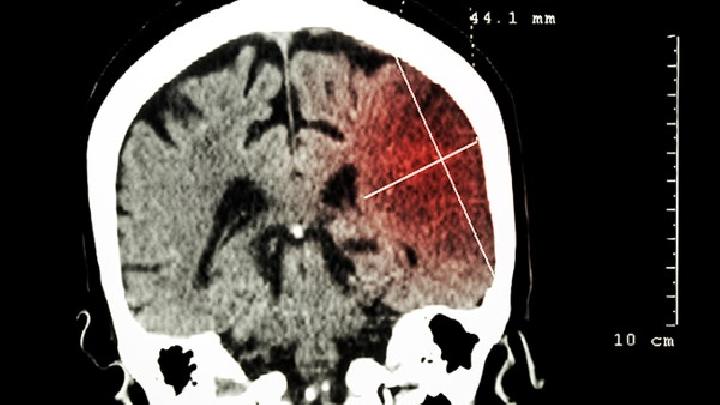

侧脑室肿瘤的症状是什么?我们可以从哪些症状来判断我们患有侧脑室肿瘤?接下来,让我们了解一下侧脑室肿瘤的相关症状。这样,当出现相关症状时,我们可以及时到医院进行相应的检查和治疗。